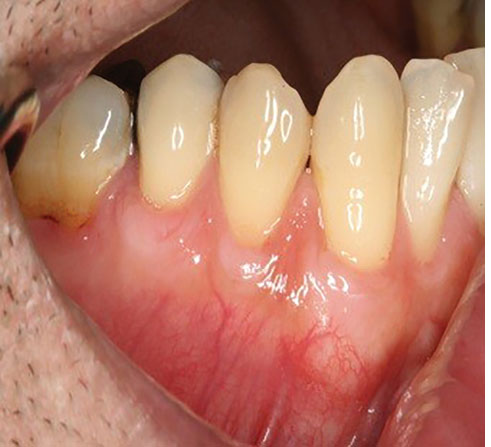

Figure 2.

SCTG site 6 months after surgery.